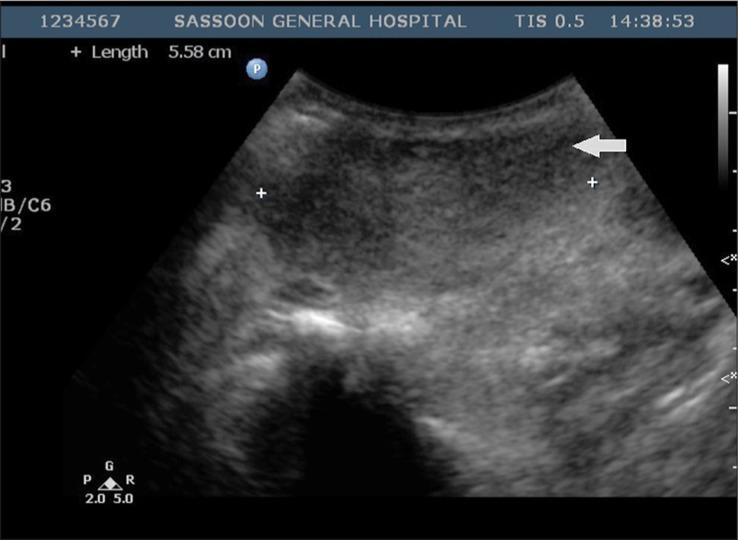

A middle-aged female patient presenting with a history of multiple chronic neck swellings was thoroughly evaluated by ultrasound (US), computed tomography (CT), and magnetic resonance imaging (MRI). The imaging findings included gross enlargement of the left parotid gland, a focal lesion in the right parotid gland, and cervical lymphadenopathy. These features correlated with histopathological findings, and the diagnosis of Kimura disease was made.

一名有多处慢性颈部肿胀病史的中年女性患者接受了超声(US)、计算机断层扫描(CT)和磁共振成像(MRI)的全面评估。影像学表现包括左侧腮腺明显肿大、右侧腮腺局灶性病变以及颈部淋巴结病。这些特征与组织病理学结果相关,从而做出了木村病的诊断。